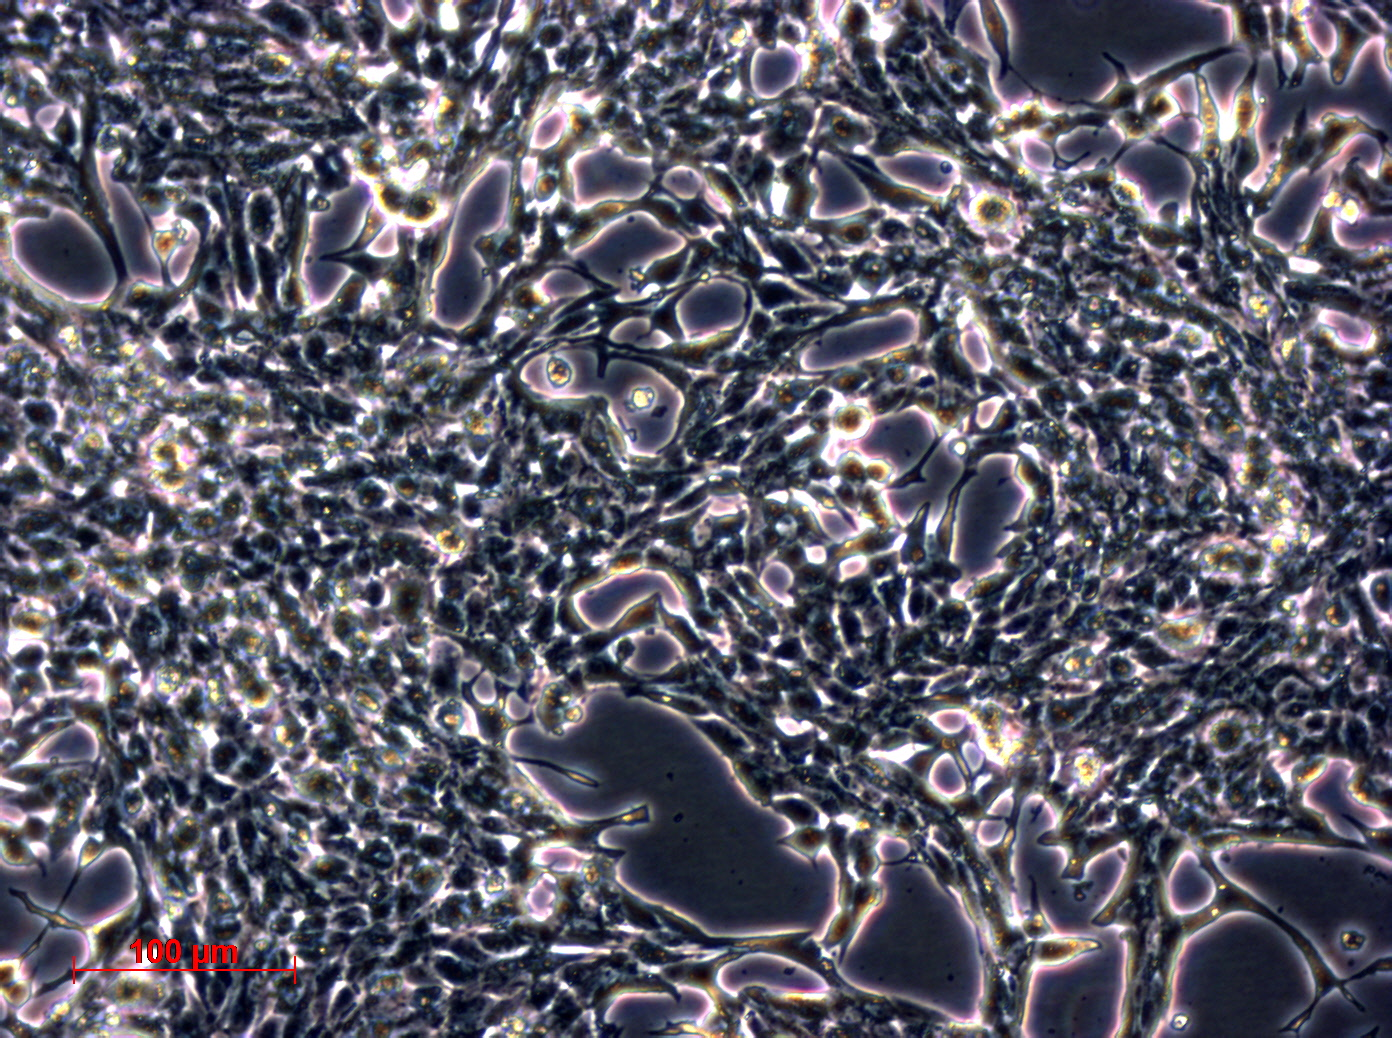

形态特征 上皮细胞样

生长特征 贴壁